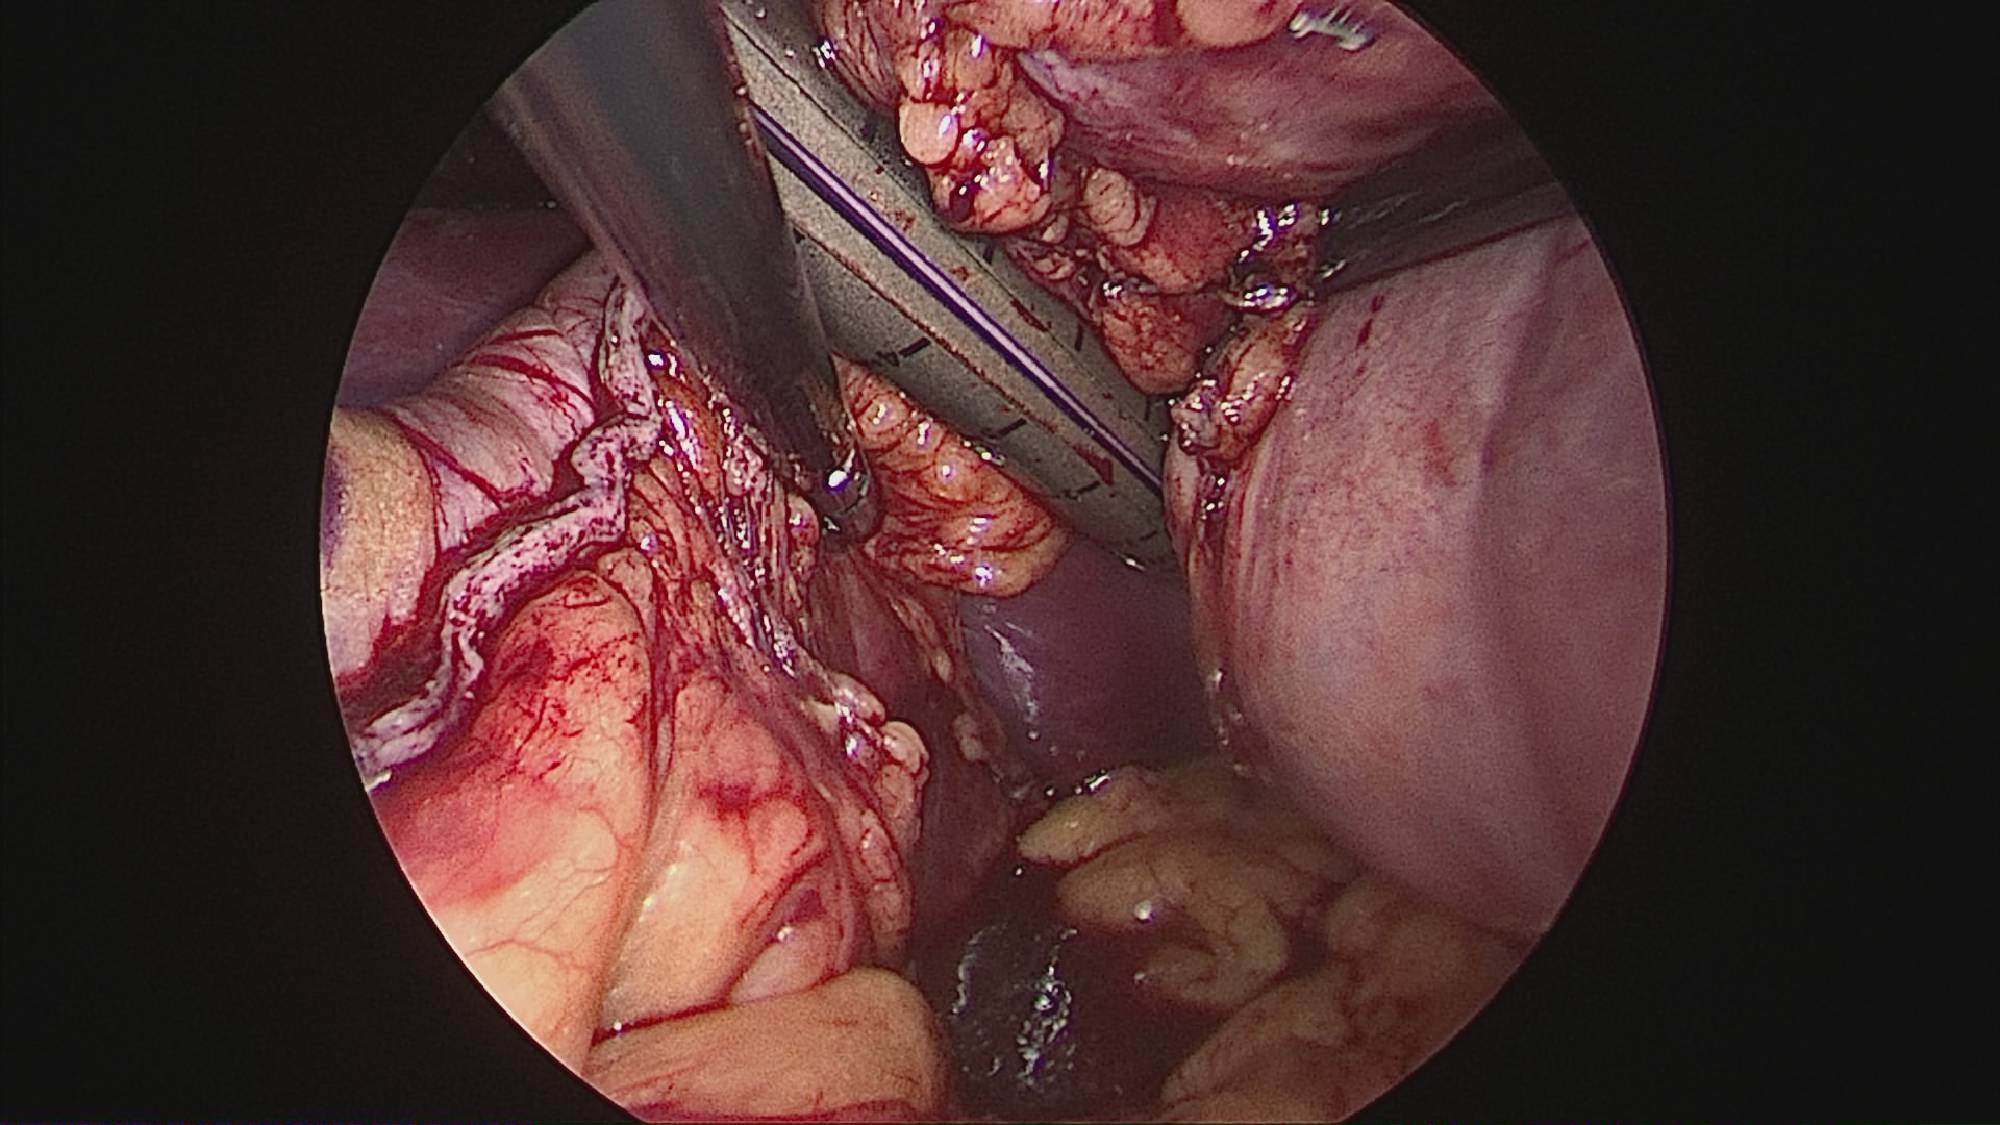

Gastrectomia longitudinală (gastric sleeve) este o intervenție care produce scăderea în greutate prin două mecanisme: restrictiv (îndepărtează o mare parte din stomac lăsând un rezervor de 80-120 ml) și hormonal (prin extirparea fundului gastric se reduce semnificativ secreția hormonului foamei, grelina).

Operația ”de micșorare a stomacului” se realizează miniminvaziv (laparoscopic) și constă în îndepărtarea marii curburi gastrice cu păstrarea antrului gastric și a micii curburi sub forma unui tub calibrat pe o sondă.

Tehnica aduce beneficiile chirurgiei laparoscopice, durere redusă, externare în primele 48 ore de la intervenție. Avantajul său constă în confortul oferit pacientului care prezintă senzația de sațietate rapid prin umplerea unui stomac de doar 100 ml, reducerea senzației de foame prin suprimarea secreției de grelina. De asemenea, nu modifică traseul alimentelor, nu exclude segmente digestive din circuit și pierderea excesului ponderal poate ajunge până la 100%.